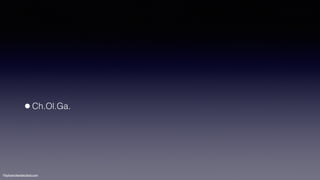

•Class II div 2

MaHe220611

•Internal root resorption of #46

©sylvainchamberland.com

•Hopeless #46